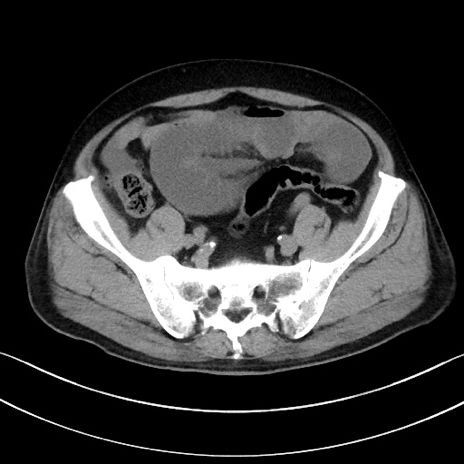

症例15(横断像)

【症例】70歳代男性

【主訴】腹痛

【現病歴】今朝から腹痛あり。全体的に痛い。特に左上の方。排ガスが今日はない。冷や汗が出る。

【既往歴】直腸癌術後

【身体所見】左側腹部〜上腹部に圧痛あり。腹膜刺激症状明らかなではない。軽度反跳痛。左下腹部に術後瘢痕あり。

【データ】WBC 7700、CRP 0.02